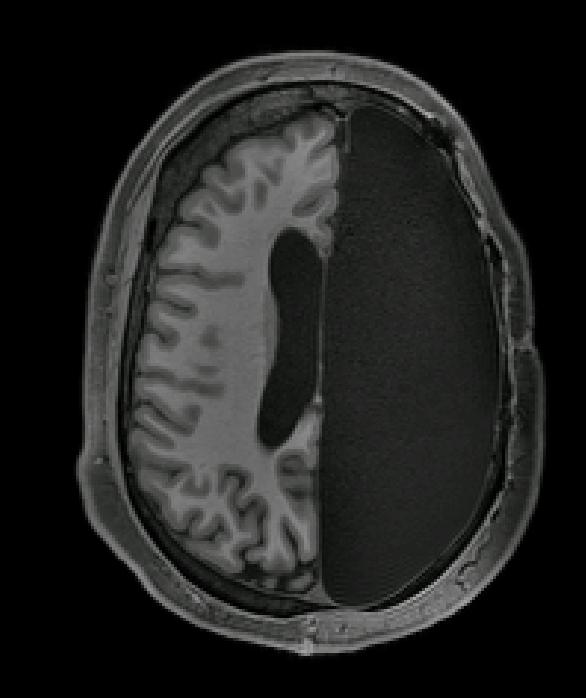

Researchers studying six adults who had one of their brain hemispheres removed during childhood to reduce epileptic seizures found that the remaining half of the brain formed unusually strong connections between different functional brain networks, which potentially help the body to function as if the brain were intact. The case study, which investigates brain function in these individuals with hemispherectomy, appears November 19 in the journal Cell Reports .

"The people with hemispherectomies that we studied were remarkably high functioning. They have intact language skills; when I put them in the scanner we made small talk, just like the hundreds of other individuals I have scanned," says first author Dorit Kliemann, a post-doc at the California Institute of Technology. "You can almost forget their condition when you meet them for the first time. When I sit in front of the computer and see these MRI images showing only half a brain, I still marvel that the images are coming from the same human being who I just saw talking and walking and who has chosen to devote his or her time to research."

Study participants, including six adults with childhood hemispherectomy and six controls, were instructed to lay down in an fMRI machine, relax, and try not to fall asleep while the researchers tracked spontaneous brain activity at rest. The researchers looked at networks of brain regions known to control things like vision, movement, emotion, and cognition. They also compared the data collected at the Caltech Brain Imaging Center against a database of about 1,500 typical brains from the Brain Genomics Superstruct Project.

They thought they might find weaker connections within particular networks in the people with only one hemisphere, since many of those networks usually involve both hemispheres of the brain in people with typical brains. Instead, they found surprisingly normal global connectivity--and stronger connections than controls between different networks.